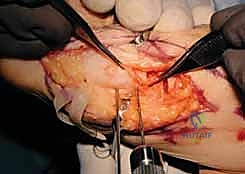

Joint Preparation and Arthrodesis

With the ulnar diaphysis resected, the ulnar head is now freely mobile, tethered only by the TFCC and ulnocarpal ligaments distally. We use a sturdy towel clip or a small bone clamp to grasp the ulnar head. By applying gentle traction and rotating the head, we gain excellent access to the articular surfaces of the DRUJ.

Using a high-speed burr or a sharp rongeur, we meticulously decorticate the articular cartilage down to bleeding subchondral bone on both the ulnar head and the corresponding sigmoid notch of the radius. It is absolutely critical during this step to protect the distal and volar attachments of the TFCC to the fovea of the ulnar head. Stripping these attachments will

Clinical & Radiographic Imaging Archive